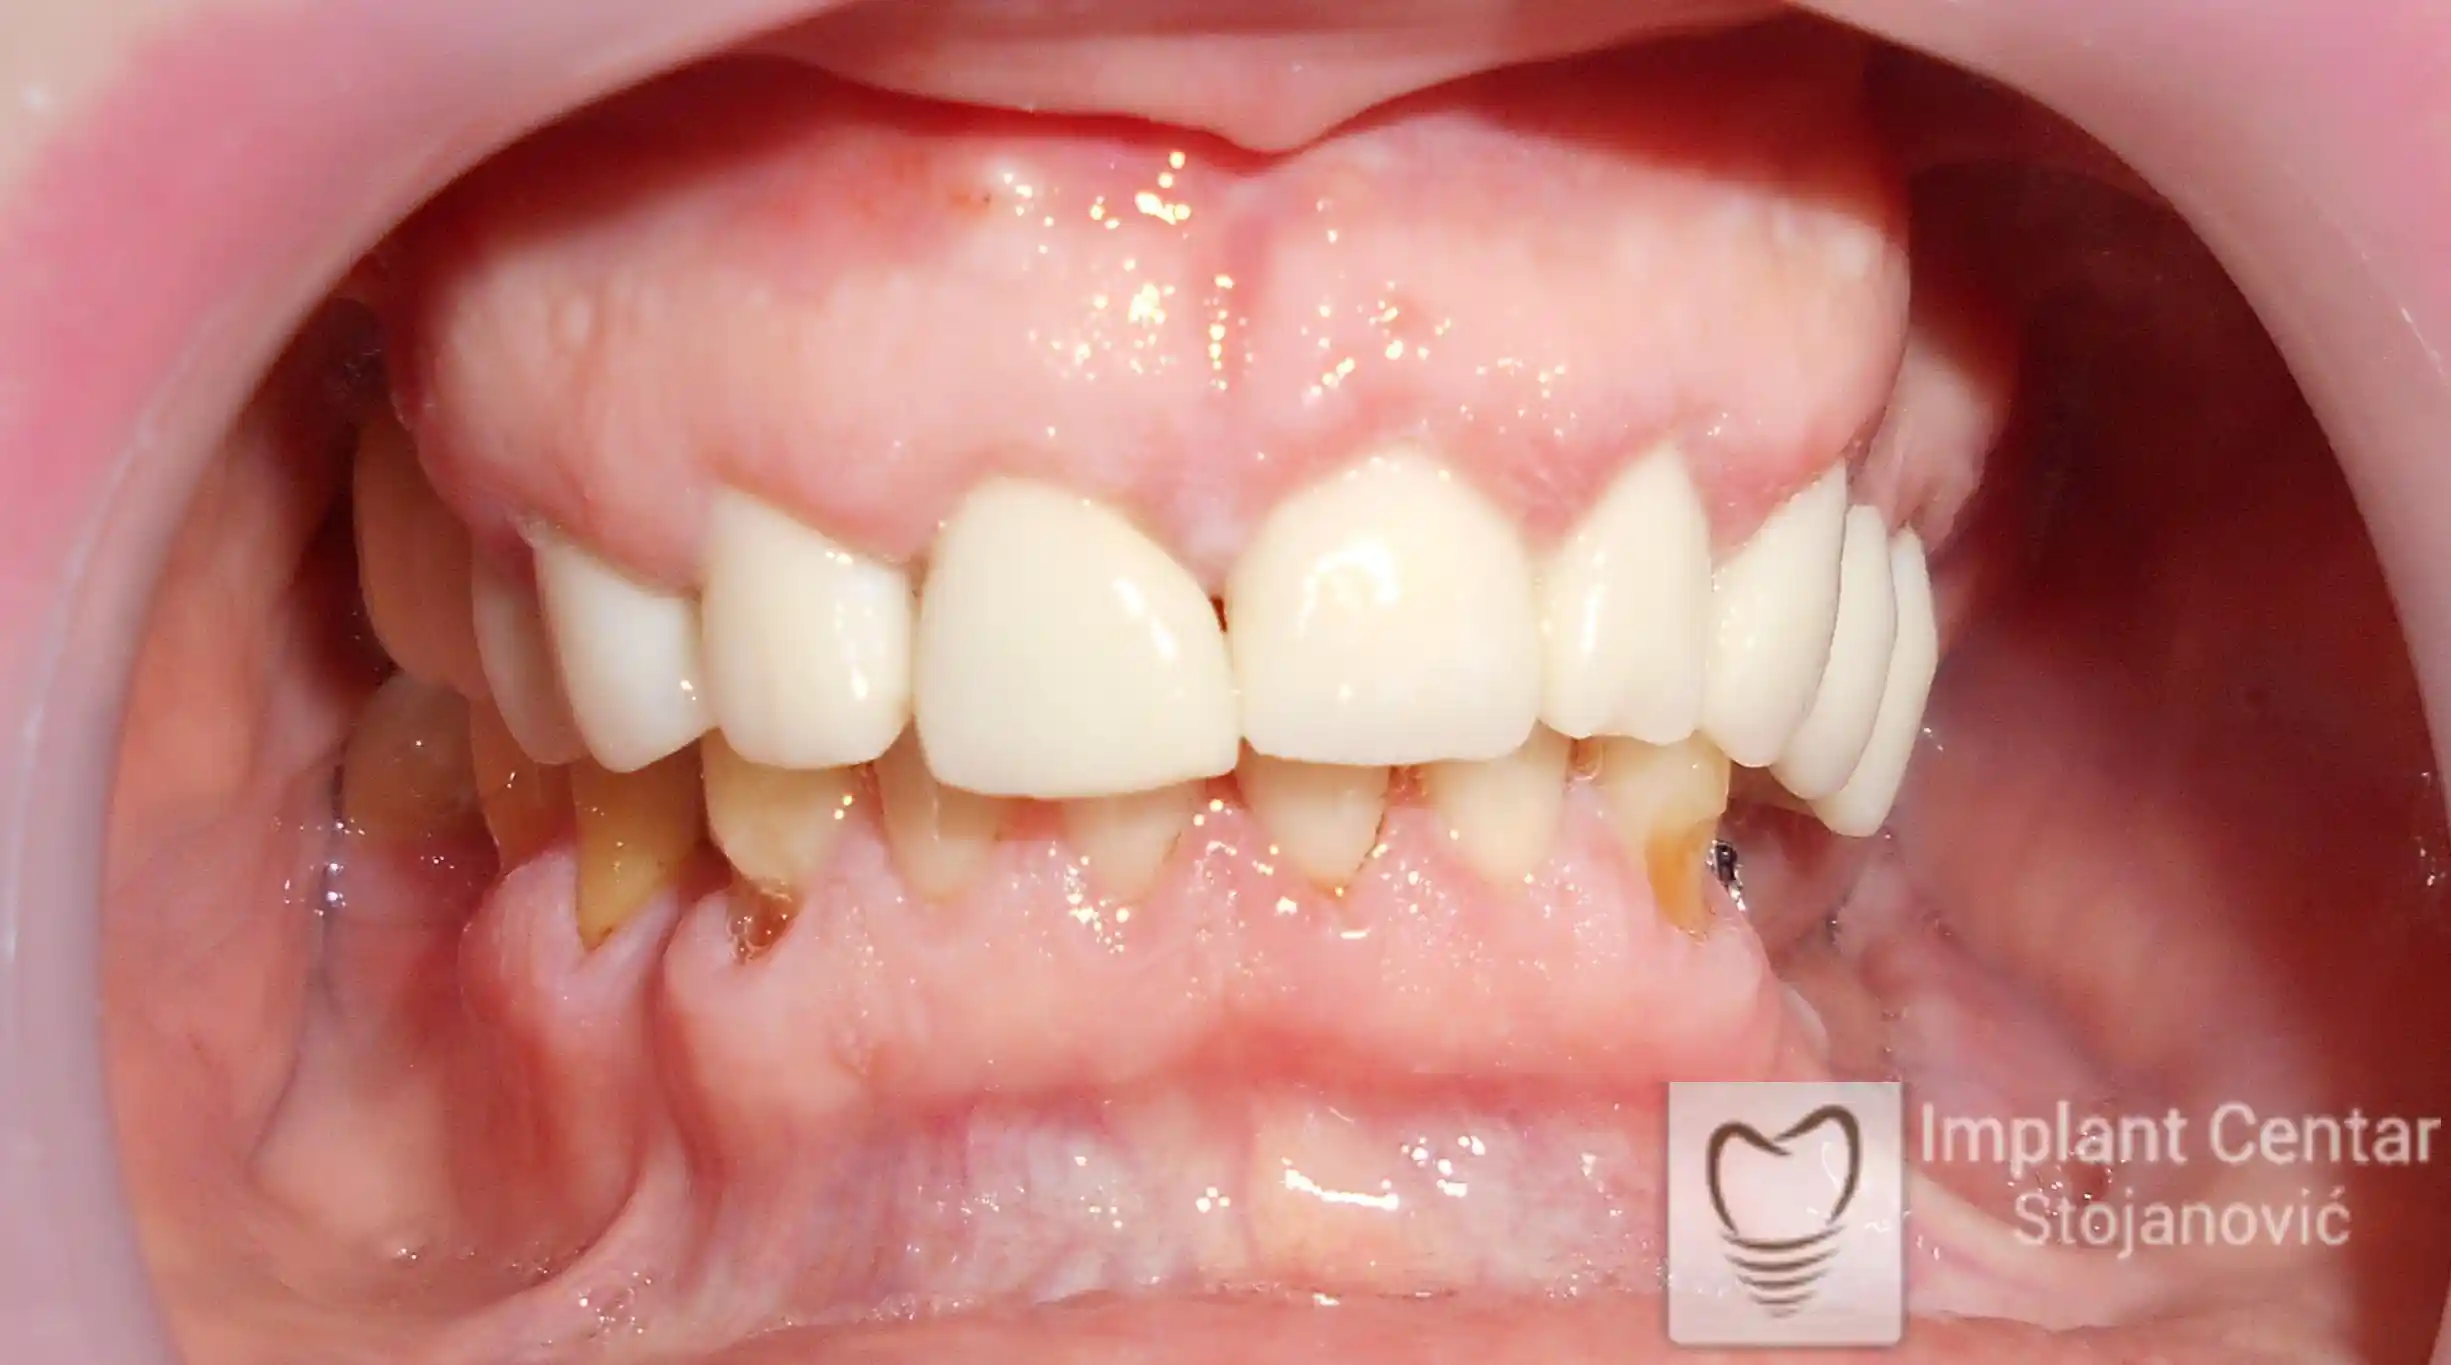

Pacijent sa rascepom usne, nepca i alveolarnog grebena uspešno je rehabilitovan fiksnim protetskim radom na implantatima. Pre dolaska u našu ordinaciju, pacijent je u gornjoj vilici nosio totalnu protezu preko preostalih zuba, dok je u donjoj vilici bio zbrinut parcijalnom mobilnom protezom. Tokom višegodišnje potrage za adekvatnim rešenjem, pacijent nije uspeo da pronađe zadovoljavajuću terapijsku opciju ni u zemlji ni u inostranstvu.

Nakon detaljnog kliničkog pregleda i analize radioloških snimaka, izrađen je sveobuhvatan plan terapije sa ciljem uklanjanja mobilnih proteza i postizanja maksimalne funkcionalne i estetske rehabilitacije. Zbog loše biološke vrednosti preostalih zuba, doneta je odluka o njihovom vađenju i ugradnji dentalnih implantata.

Poseban terapijski izazov predstavljalo je premošćavanje defekta nastalog usled rascepa, kao i ograničena količina raspoložive kosti u gornjoj vilici. Primenom većeg broja implantata i odgovarajućih procedura nadoknade kosti, postignuta je stabilna osnova za fiksni protetski rad.

Tokom perioda oseointegracije, pacijent je bio zbrinut fiksnim privremenim krunicama, čime je već pet dana nakon intervencije obezbeđena potpuna funkcionalna i estetska rehabilitacija. Nakon završetka perioda integracije implantata, izrađeni su definitivni cirkonijum-keramički mostovi na implantatima.

Pacijent je izuzetno zadovoljan postignutim rezultatom, navodeći da po prvi put jasno oseća svoje nepce tokom žvakanja, kao i da se smeje sa punim samopouzdanjem.